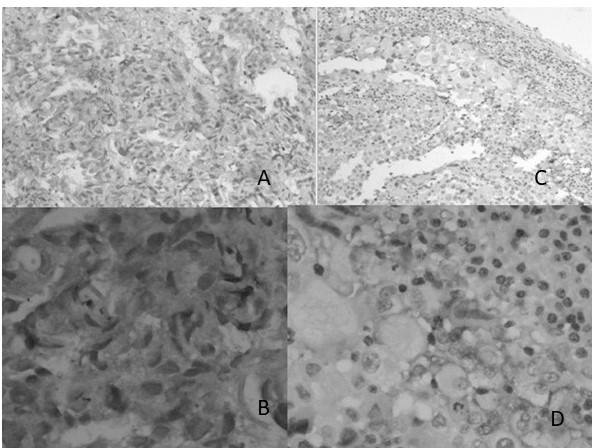

Histológicamente el inmunomarcaje de EGFR mostró un patrón de tinción citoplasmático con la intensidad similar a los controles como es esperado (Figura 2).

La positividad para ALK se observó en 24,13 % de los casos, de este total 10,34 % expresaron positividad focal. En el material revisado la mayor parte de los casos positivos mostraron expresión citoplasmática fuerte y 3 casos observados mostraron inmunomarcaje focal de menor intensidad 10,34 pos focal, 13,70 % positivos y 75, 86 % negativos.

Los casos evaluados como positivos expresaron en su mayoría una tinción de fuerte 3+ a positiva moderada 2+. Se observó en algunos casos patrón de tinción de interfaz y patrones positivos focales aun considerándose positivo. Todos los casos positivos presentaron positividad en más del 1 % de las células tumorales (Figura 4).